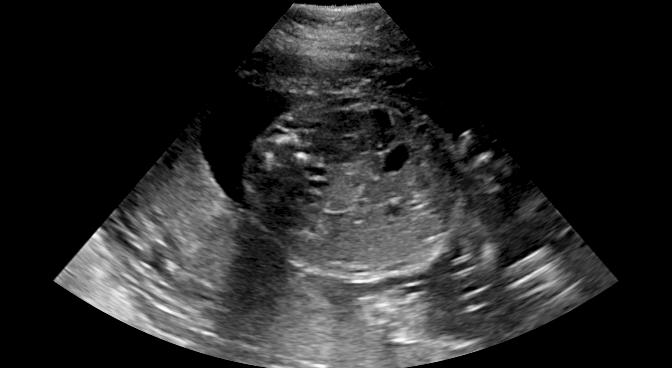

Sound-opaque occluders, including bones and calcified tissues, block the propagation of sound waves by strongly absorbing or reflecting sound waves during scanning. The regions behind these sound-opaque occluders return little to no reflections to the US transducer. Thus these areas have low intensity but very high acoustic impedance gradients at their boundaries (e.g. Fig. 1(a) left column). Reducing acoustic shadows and correct interpretation of images containing shadows rely heavily on sonographer experience. Experienced sonographers avoid shadows by moving the probe to a more preferable viewing direction during scanning or, if no shadow-free viewing direction can be found, a mental map is compounded with iterative acquisitions from different orientations.

Fig. 6 compares the shadow confidence maps of the state-of-the-art methods and the proposed methods. RW and have the same parameters as used for Table I. The shadow confidence maps of the baseline, the proposed method and the proposedAG method are generated directly from input shadow images by confidence estimation networks. Overall, the proposed method and the proposedAG method achieve more visually reasonable shadow confidence estimation than the baseline and the state-of-the-art on different anatomical structures shown in Fig. 6. The proposed method and the proposedAG method are able to highlight multiple shadow regions while the RW algorithm shows limitations for most cases, especially for disjoint shadow regions.

Row I in Fig. 6 shows a fetal brain image from . The confidence estimation of shadow regions from the baseline, the proposed method and the proposedAG method are similarly accurate since we use fetal brain images to train the confidence estimation networks in these three methods. These outperform [16] and [22]. Rows (II-IV) in Fig. 6 show shadow confidence maps of non-brain anatomy from , including lips, abdominal and cardiac. The baseline failed on unseen data during inference. However, the proposed methods are able to generate accurate shadow confidence maps because of the generalized shadow features obtained by the shadow-seg module. Furthermore, the “Lips” example shows that our method is capable of detecting weaker shadow regions that have not been annotated in manual segmentation. This indicates that the confidence estimation network has learned general properties of shadow regions.